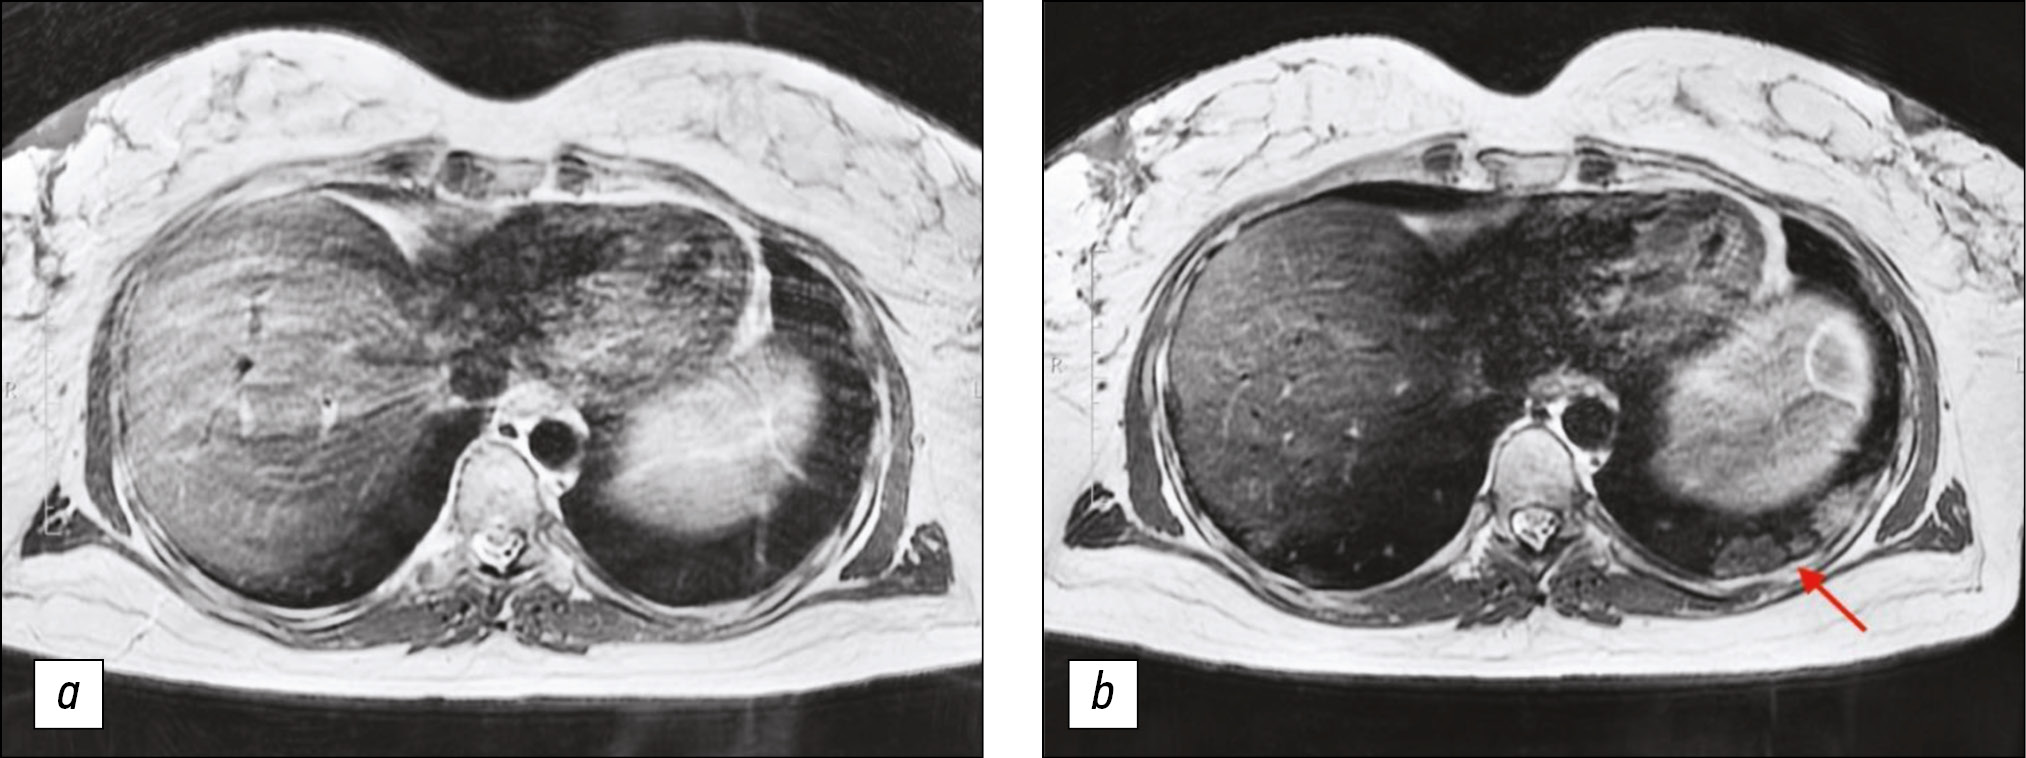

Lung MRI was performed 7 days later, because the condition did not improve during treatment, and dry, ineffective cough worsened. MRI performed that time revealed zones of infiltration (Figs. 1, 2) in the lower lobes of the lungs.

Figure 2. Chest magnetic resonance imaging, T2-weighted imaging single-shot fast spin echo: a) Primary examination, b) magnetic resonance imaging 7 days later. In Fig. 2b, consolidation zones in the lower right lung appeared as areas of hyperintense signal.